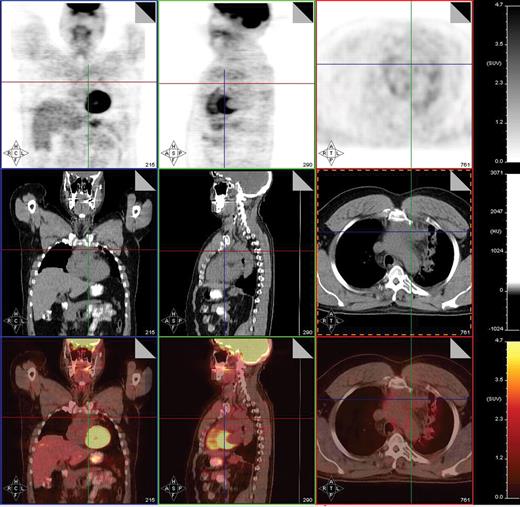

Post-treatment PET/CT scan performed 2 months after treatment with 8 cycles of AVD followed by involved field radiation therapy in a patient with stage IIA mixed cellularity Hodgkin lymphoma showing a PET-negative residual mass in the mediastinum measuring 4.2 × 2.9 cm. PET/CT was otherwise negative. This patient is currently without evidence of disease after 23 months of follow-up post therapy.